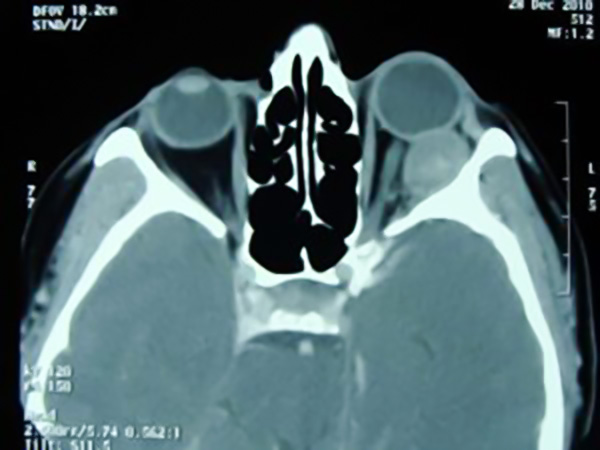

Orbita tümörü, göz çukurunda bulunan yapılardan köken alan tümörlerdir. Orbita tümörleri iyi huylu (benign) veya kötü huylu (malign) tümörler olabilir. Bu bölgede göz ve görme ile ilgili önemli yapılar bulunduğundan, tümör iyi huylu da olsa görmeyi bozucu etkiler oluşturabilir.

Orbita tümörlerinde ilk ortaya çıkan belirti, kitlenin yer kaplayıcı etkisi ile gözü ve çevresindeki yapıları öndeki açıklıktan dışarı itmesi ve gözün ileriye doğru çıkmasıdır (proptozis). Tümörün yerleşimine göre göz küresi, diğer göze göre, daha aşağıya veya daha yukarı da itilmiş olabilir. Orbita içerisinde yer alan yağ dokusunun öne doğru itilmesi kapaklarda ve kaş altında şişliğe yol açabilir.

Ayrıca kitle ve çevresindeki reaksiyona bağlı olarak veya gözde ileri doğru itilmenin oluşturduğu gerginlik nedeniyle görme siniri hasar görebilir, yapısal ve fonksiyonel kayıplar gelişebilir. Klinik belirtileri, etkilenen gözde görmenin azalması/kaybı, görme alanında perdelenme ve renk görmenin bozulmasıdır. Gözü hareket ettiren kaslardan kaynaklanan veya bu kaslara bası yapan tümörlerde, kas fonksiyonları etkilenir. Görme bulanıklığı, çift görme veya kitle etkisine bağlı olarak baş ağrısı görülebilir. Gözyaşı bezinin etkilendiği tümörlerde gözde kuruluk hissi gelişebilir ve üst kapak dış kısmı aşağı doğru sarkar (yatay S harfi şeklini alır).